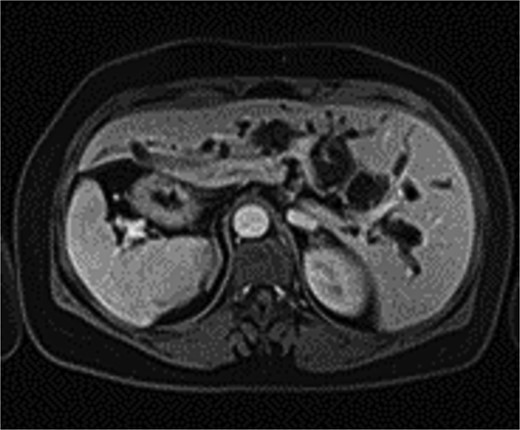

Intraoperatively, the liver was located on the left side, with the spleen and stomach on the right. The surgeon stood on the patient’s right side, with the patient in a reverse Trendelenburg position (30° head-up, 15° left-side down). Adhesions between the liver, omentum, and surrounding organs were carefully dissected to expose the common bile duct, which measured 2.0 cm in diameter. A 1.5 cm longitudinal incision was made on the common bile duct, and stones were extracted using atraumatic forceps and a stone retrieval basket. Choledochoscopy confirmed no residual stones in the intrahepatic or extrahepatic bile ducts. Due to marked edema at the lower end of the common bile duct caused by stone impaction, a 22 French T-tube was placed. The procedure lasted 125 minutes, with no postoperative bile leakage or other complications. The patient had an uneventful recovery and was discharged on postoperative day 5. Two weeks later, cholangiography showed no residual stones in the bile duct (Fig. 3).

Postoperative cholangiography shows no residual stones in the bile duct.